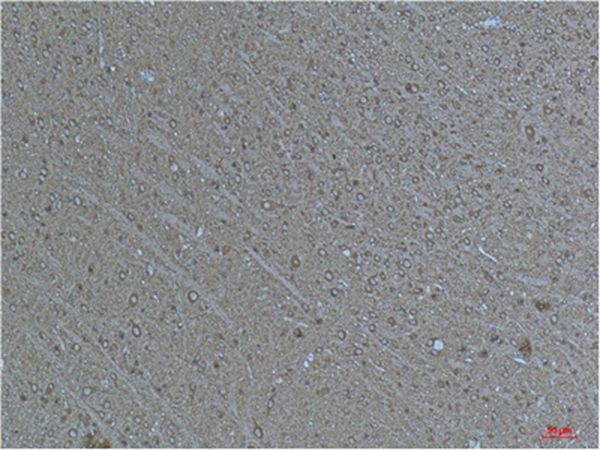

分类: 科研抗体货号: P43824别名: Transcription factor p65 (Nuclear factor NF-kappa-B p65 subunit) (Nuclear factor of kappa light polypeptide gene enhancer in B-cells 3)应用: IHC反应种属: Human,Mouse,Rat